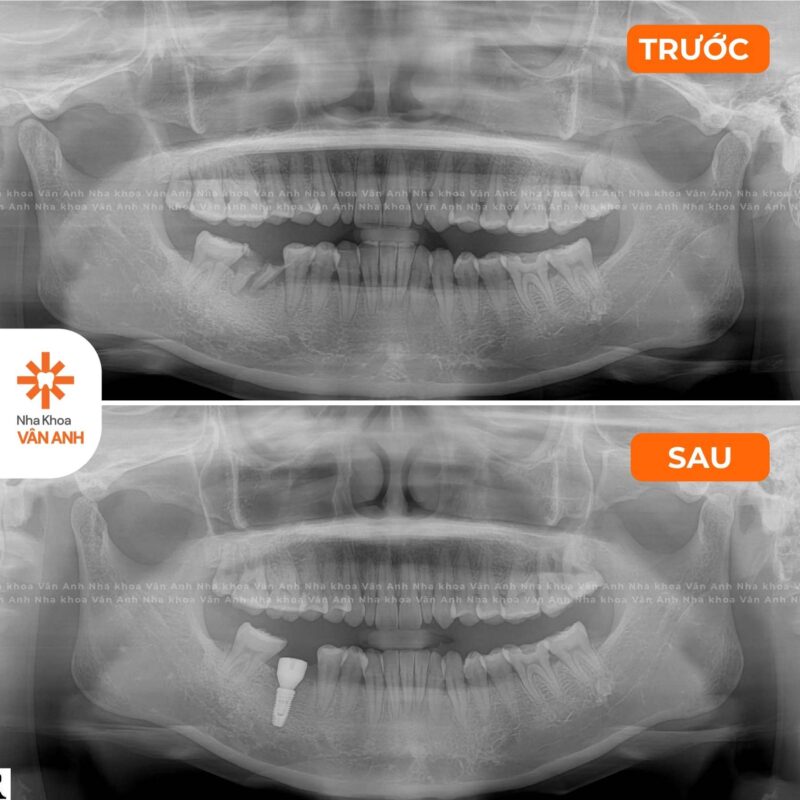

Lĩnh vực chuyên sâu: Phục Hình – Tiểu Phẫu

- Chứng chỉ Cắm Ghép Implant Nha Khoa – Viện Đào tạo Răng Hàm Mặt, Đại học Y Hà Nội.

- Chứng nhận đào tạo Cấy ghép implant Nha khoa nâng cao: Implant tức thì và Implant vùng thẩm mỹ – Viện Đào tạo Răng Hàm Mặt, Đại học Y Hà Nội.

- Chứng nhận đào tạo Nâng xoang GBR – Dentium Academy